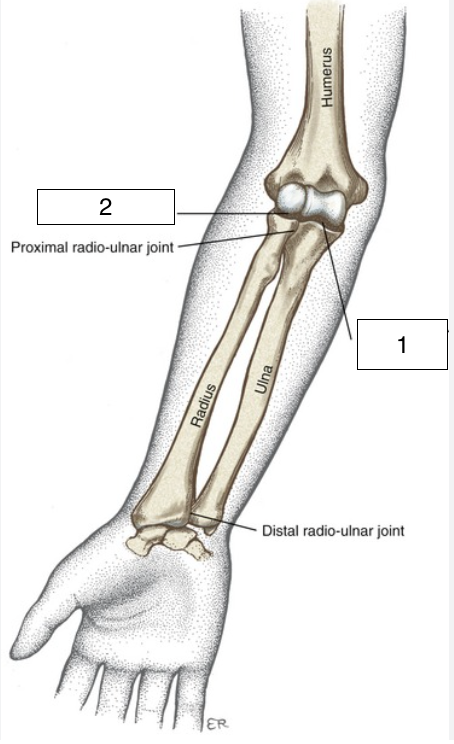

what is the highlighted joint (number 1)?

proximal radioulnar

what is the highlighted joint (number 2)?

distal radioulnar

what kind of joints are the proximal and distal radioulnar joints?

synovial, pivot joint